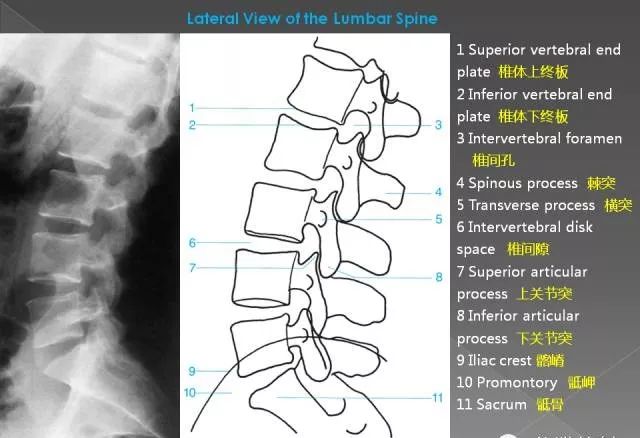

2、侧位片

可观察腰椎曲度,腰骶角大小,椎体有无压缩、楔形变,还可观察测定椎体指数,椎间隙大小,椎间孔大小等。

(1)正常腰椎曲度:自T12椎体后下缘至骶。椎体后上缘作一连线,另沿各腰椎体后缘作弧状线,二者形成弓形。正常弓顶在L3椎体,二线间最大距离正常为1.8~2.2cm,代表腰椎曲度。腰椎过度前凸时致弓顶距离增大,则此时T12垂线亦后移使腰椎前凸指数加大,身体重心后移,小关节负荷重易劳损及退变。腰痛者腰前凸常因代偿性腰椎变直而减小。

(2)腰骶前弓角:分别做L3椎体,L5椎体和Sl椎体的对角连线,对角线交点分别为各椎体中心。连接L3和L5椎体中心,L5与Sl椎体中心,两直线后方交角为腰骶前弓角,平均:146°(124°~162°)。立位或卧位变化不大。

腰椎曲度正常则重力线在正常位置,无需肌肉、韧带用力即能直立。腰椎过度前突则重力后移,小关节所受剪力增加致局部肌肉韧带劳损,小关节发生退行性改变甚至半脱位,继之椎间盘负荷加重发生退行性变,还会增加椎弓峡部压力,都会引起下腰痛和腰椎不稳定。

(3)椎体指数常用于测量L5椎体楔变程度。计算方法为:椎体指数=L5后缘高/L5前缘高。正常大于0.80,如小于0.80,则易造成峡部疲劳骨折。故常见于椎弓崩裂者。

(4)椎管矢状径:矢状径的大小可反映椎管发育性狭窄程度,测量时先找出椎管后界,在腰椎侧位片因与横突重叠,常显示不清。测定方法为:L1-3为上、下关节突尖连线,L4为此连线向后1mm,L5为棘突弓状透明缘向前1mm。此线与椎体后缘中点连线长度为矢状径。正常此矢状径皆大于17mlm,椎管狭窄者常小于15mm,因而可认为矢状径小于15mm者为狭窄性椎管,小于17mm者为较小椎管。较小及狭窄椎管易因退变增生而引起椎管狭窄症。CT扫描测量骨性椎管的大小,方便、准确。怀疑骨性椎管狭窄时可做CT扫描。

(5)椎弓根上切迹:指侧位片上椎弓根在椎体上缘水平的长度,亦即椎体后上缘与上关节突水平间距,正常大于5mm。椎弓根上切迹小者往往表示椎弓根短,常见于发育性侧隐窝狭窄者。

(6)椎间孔,骨性椎间孔自上而下逐渐变窄,至L5常呈耳形。单个椎间孔变大见于神经纤维瘤患者。正常下位椎体上关节突尖不高于上位椎体下缘水平,椎间盘退变后关节突可向上交错,如进入椎弓下切迹,易嵌压走行于其中的神经根。

(7)椎间隙,侧位片可显示椎间盘所在空隙。在腰椎此间隙自上而下逐渐增大椎间隙在L5S1间前宽后窄,以适应腰骶角,椎间盘退变时,L4-5或L5S1间隙可变窄,但间隙变窄与椎间盘突出并不等同。青壮年的椎间盘的局部突出并不一定能显出椎间隙狭窄。

(8)上关节突水平位置:经任一椎体下缘终板做终板平行线,其向后延长线在下一脊椎上关节突顶点之上。如果上关节突超过此线可能有半脱位或椎间孔和侧隐窝减小。此线最初是在卧位X线片上测定,立位时是否如此不能肯定。

(9)腰椎滑椎分级:将骶骨底上缘前后径分为四等份,观察L5椎体后下角位置。正常时L5后下角和骶l后上角相对或稍后。椎体向前滑脱则L5后下角影像前移。向前滑脱分4级。1级,L5后下角与最后一段相对;2级,后下角对第2段,以此类推。此分级法也适用于其他椎体滑脱。

(10)关节突连续曲线:在X线正位及斜位像上,沿横突下缘、下关节突外缘,跨过小关节腔再沿相对上关节突外缘的连续弯线呈光滑、自然的抛物线;关键是圆滑匀称地经过关节突部位。若弧线突然变形提示小关节半脱位。